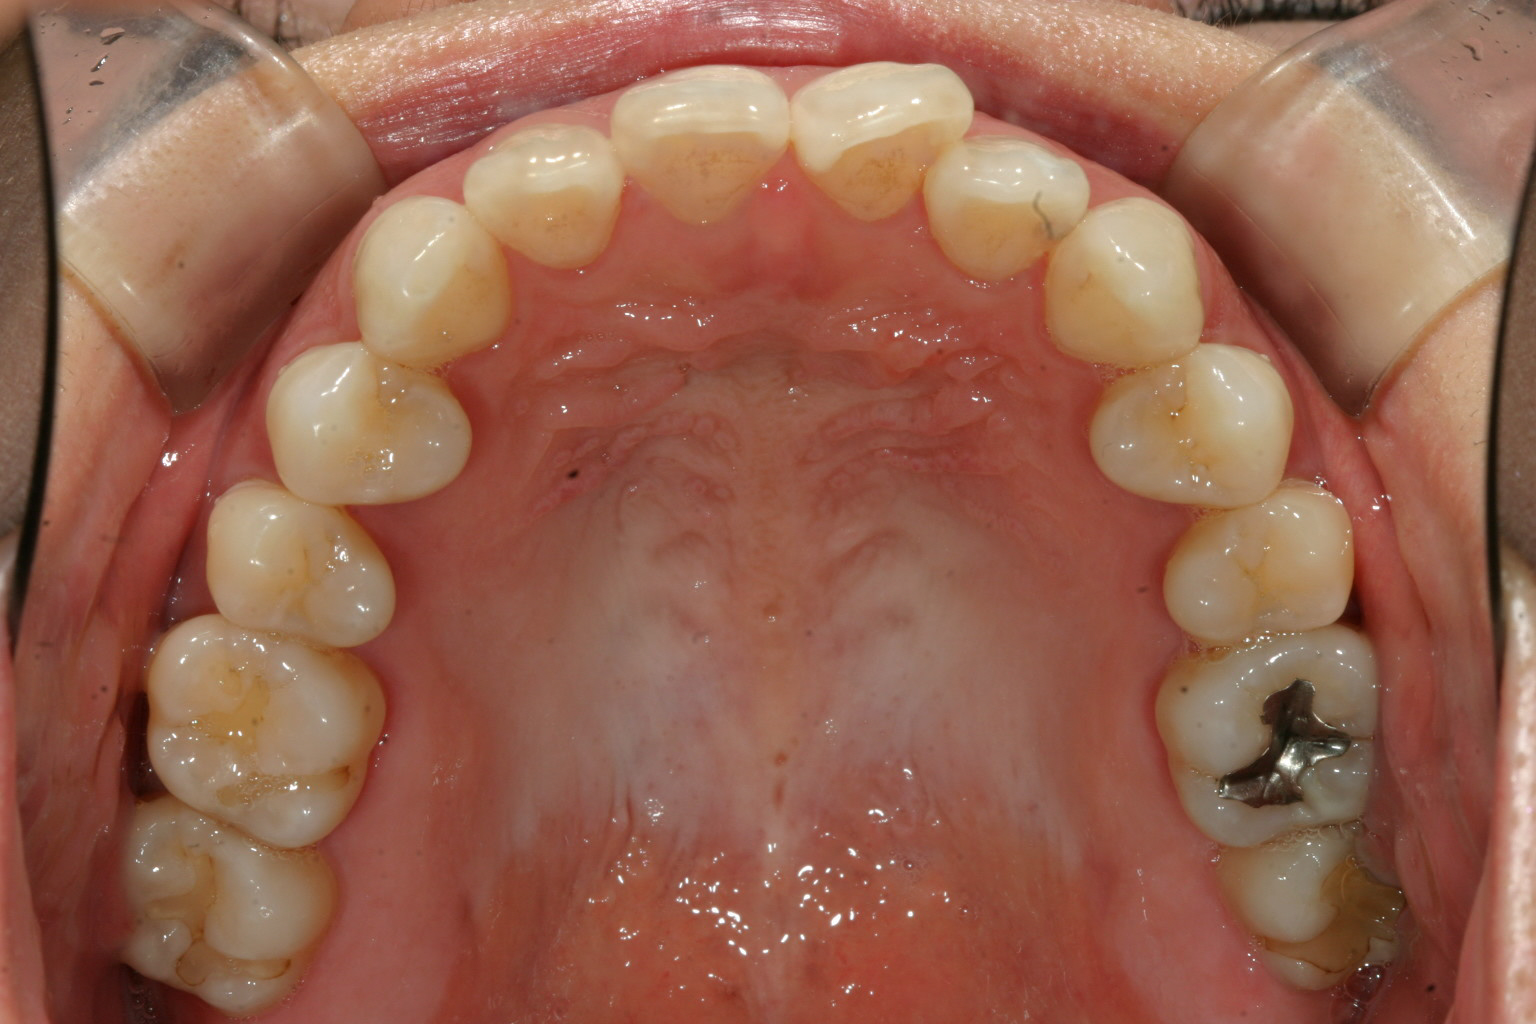

少し前歯が翼状捻転してますがそんなに悪くないですね~

全体的に綺麗な歯列ですが1歯だけ気になりますね~

少し受けてますね~ 上顎の歯列もさほど乱れがなく受け口と言うのは少し厄介でガタガタなら綺麗に並べれば全体的に歯列は前に出ますが、綺麗な歯並びだと前には出てくれません。